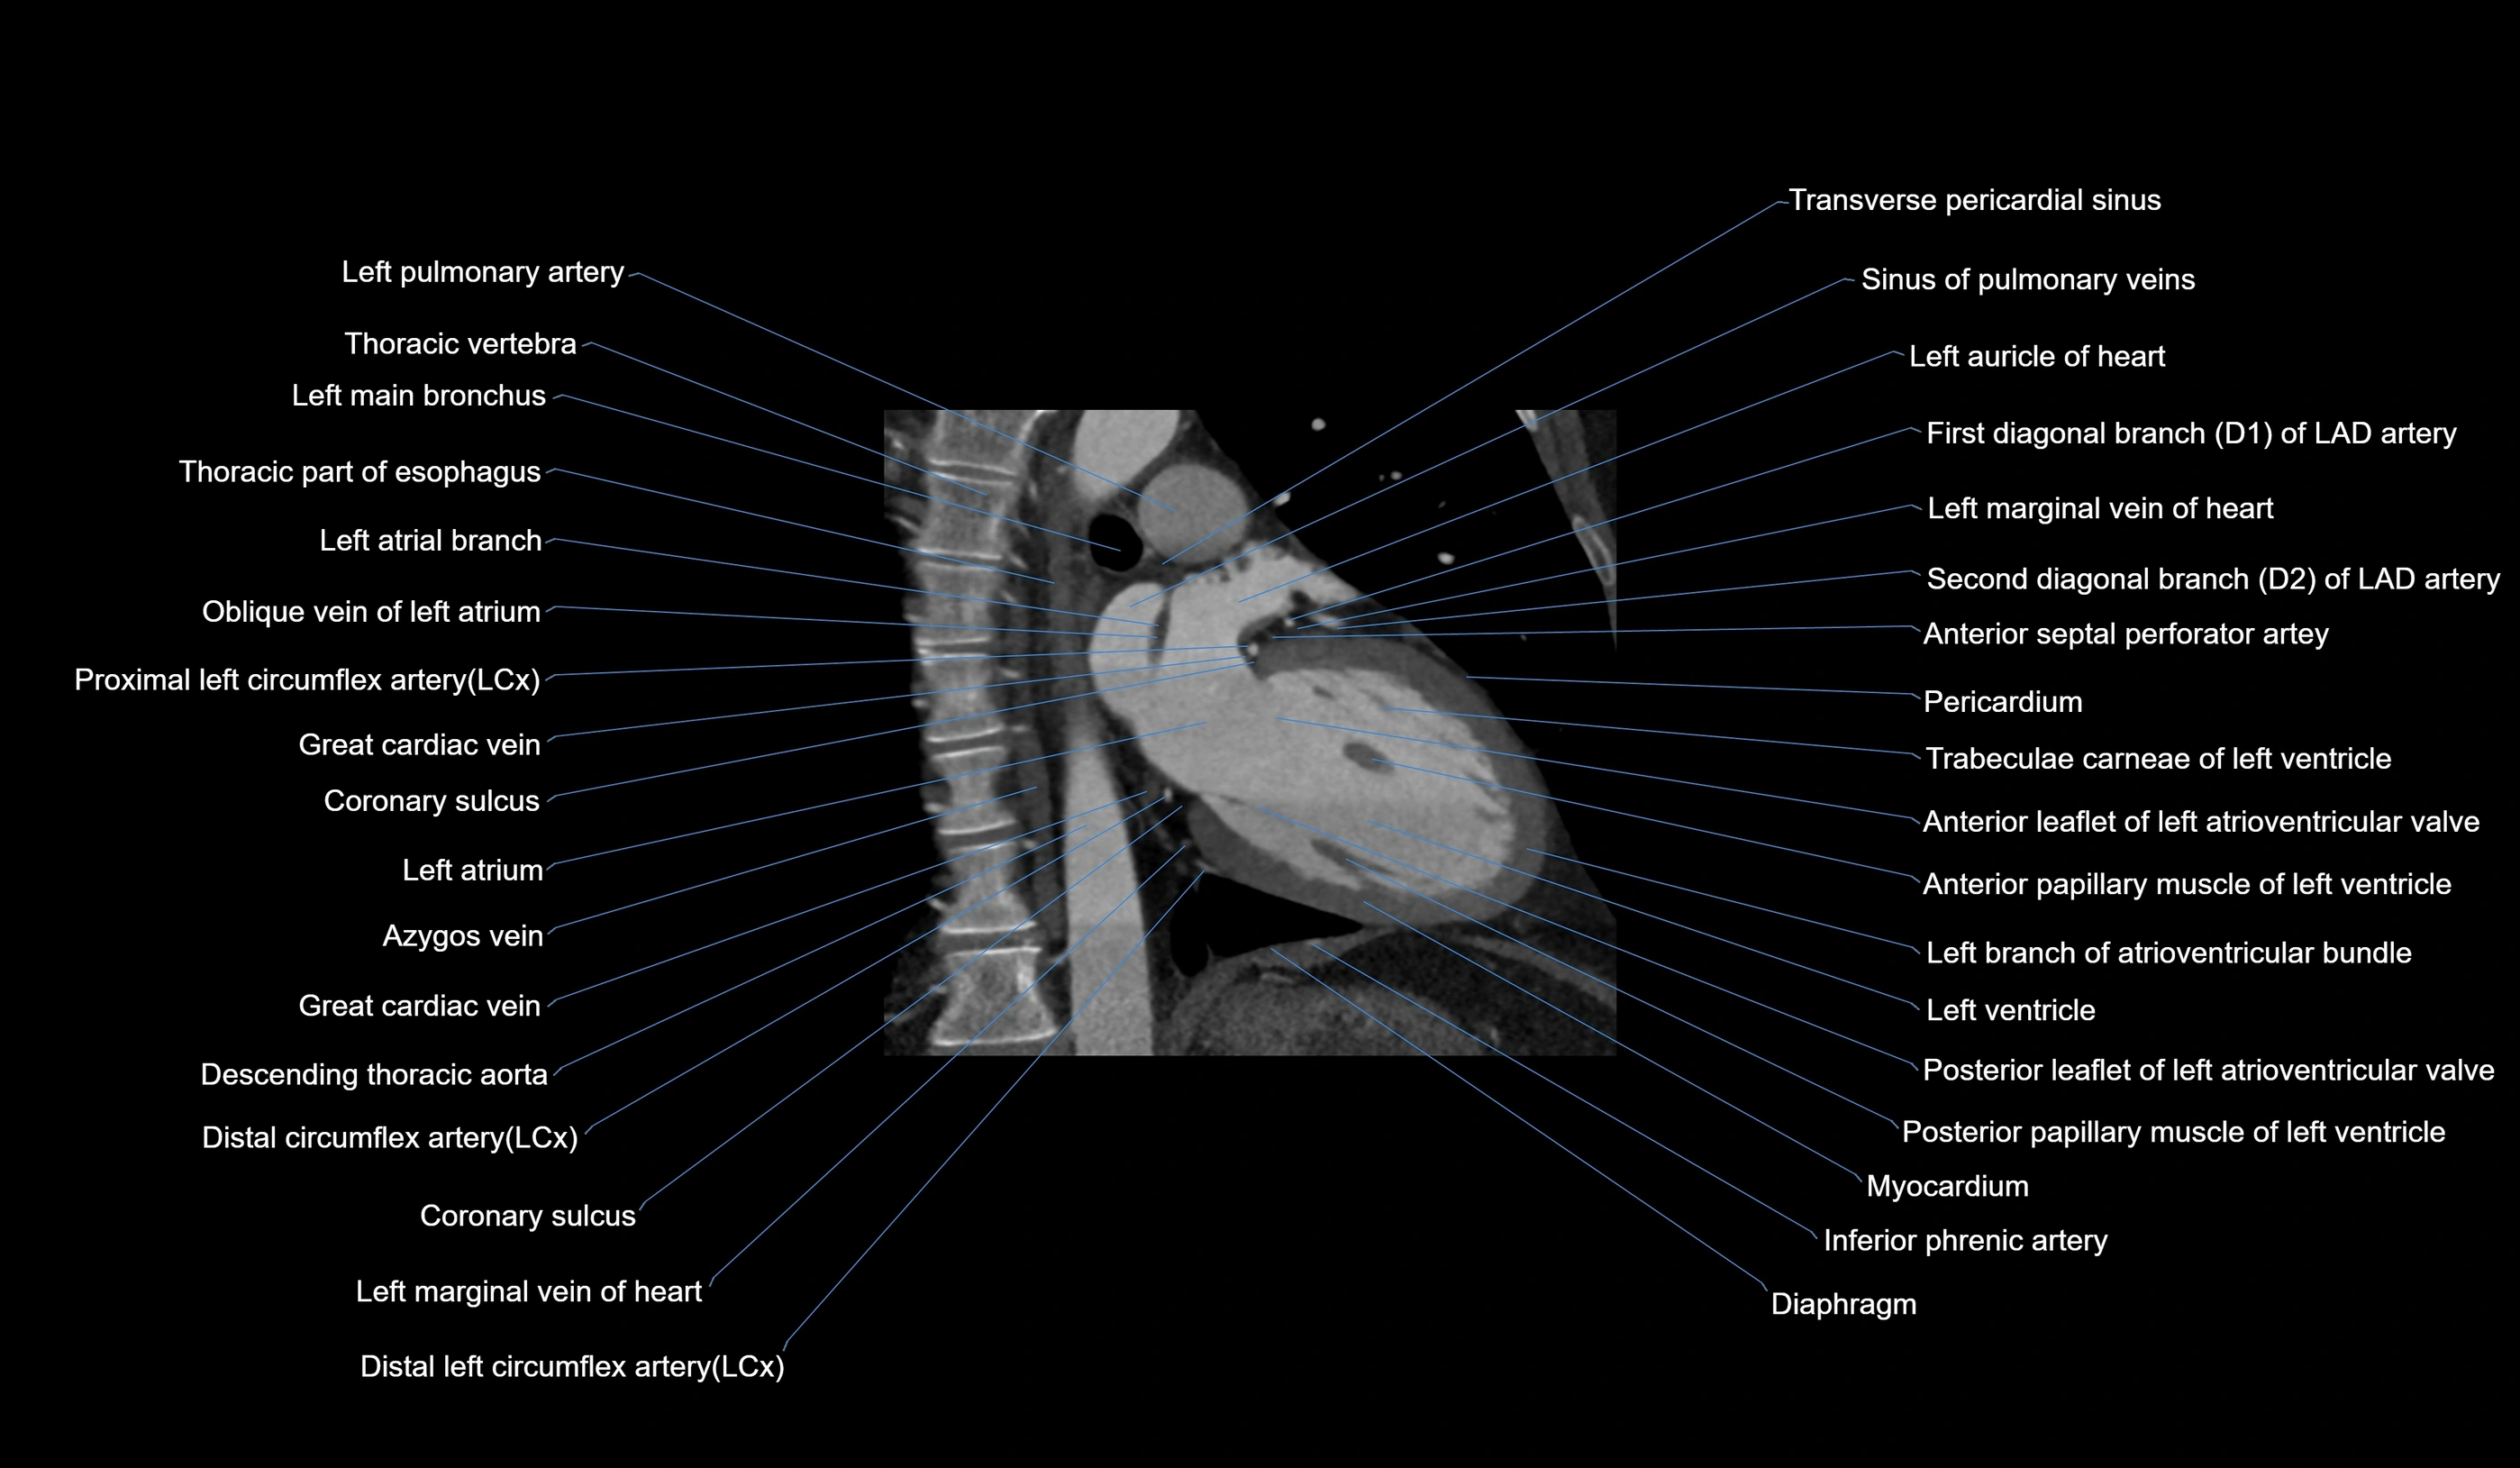

- Acute marginal artery (AM)

- Anterior interventricular sulcus

- Anterior leaflet of left atrioventricular valve

- Circumflex artery (LCx)

- Coronary sulcus

- First diagonal branch (D1) of LAD

- Great cardiac vein

- Left atrial branch (coronary artery)

- Left atrium

- Left auricle

- Left branch of atrioventricular bundle

- Left main bronchus

- Left marginal vein

- Left pulmonary artery

- Left ventricle

- Oblique vein of left atrium

- Posterior leaflet of left atrioventricular valve

- Second diagonal branch (D2) of LAD